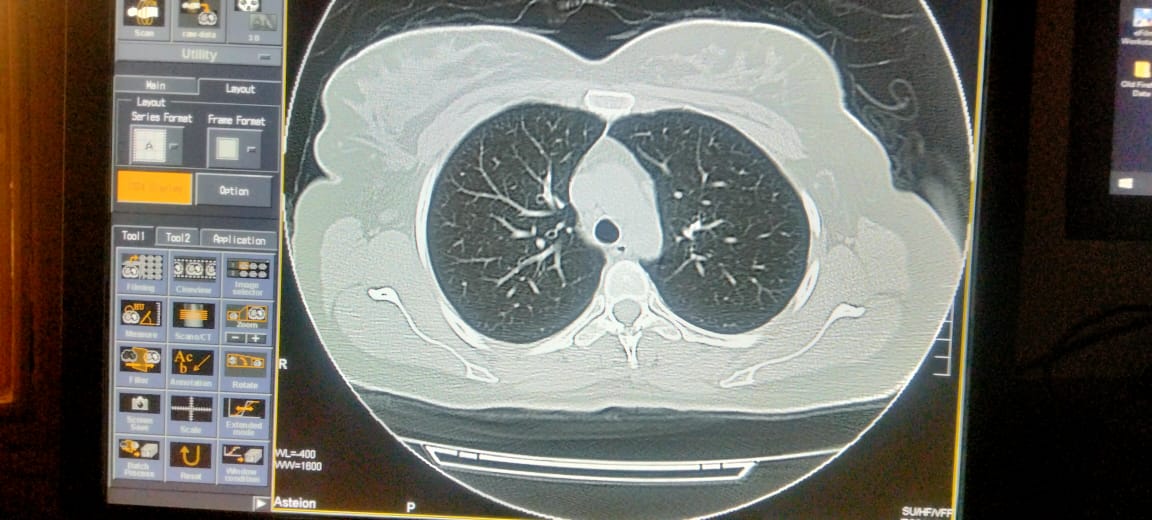

Asking for Sister, Female, 33 years old, Isl

Plz describe it. Film of hrct of corona patient

plz contact radiologist

Send full films, its incomplete